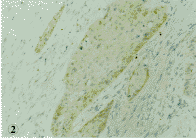

正常食管粘膜上皮细胞中可见部分细胞表达P16蛋白,主要分布于基底层,棘细胞层亦可见P16蛋白少量的表达。在50例食管鳞状上皮癌中仅见10例为P16蛋白阳性,其中弱阳性(+)者(图2)为5例,中等~强阳性(+ +~+ + +)者5例,阳性部位主要位于胞核(图2),亦可见胞浆者(图1),P16蛋白阴性40例。

图2 食管鳞状上皮癌(Ⅱ级),P16阳性,可见癌巢中癌细胞核呈弱阳性表达,免瘦组化染色,100×

Fig. 2 Esophageal squamous cell carcinoma (grade Ⅱ). P16 shows weak reactivity in the nuclus of tumor cel1s, 1mmunohistochemical staining. 100 ×